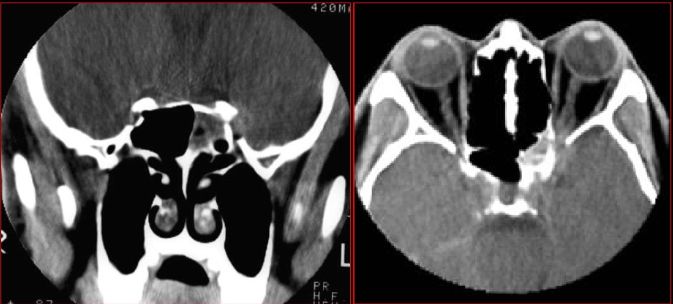

慢性多发鼻窦炎鼻息肉